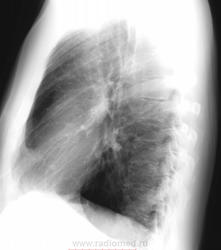

Мужчина 1966 года рождения, жалоб не предъявляет, на плановой ФЛГ выявлены изменения, дообслндование...

2 года назад на ФЛГ без изменений (по описанию, пленки нет), со слов год назад на ФЛГ изменений не находили (результатов нет).

Очень сомнительно,что была норма,скорее всего,был пропуск.Похоже на туберкулёму в S9 слева.

А у меня такое мнение, что с гамартомой дифференцировать надо. А по поводу тактики- рисуем в заключении круглую тень, предпологаете диф. ряд. и к терапевту (нарисовать направление к торакальным хирургам) ИХМО.

Округлое образование, похоже не зло. Консультация фтизиатра, торак. хирурга. Возможно и не пропуск был, установка с разворотом, может в прошлый раз стоял ровно и тень наложилась на тень сердца

Неоднородное образование, контур неровный. Первое - гамартома, наблюдение или сразу КТ. Дальше все равно наблюдение.

На зло совсем не похоже, присоединяюсь к мнениям о гамартоме и туберкулеме.. P.s. Трансторакальная биопсия при таком расположении это жестоко